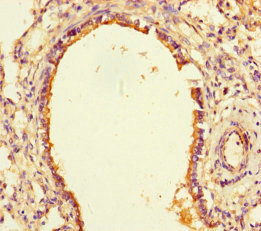

Immunohistochemistry of paraffin-embedded human thyroid tissue using CSB-PA867155LA01HU at dilution of 1:100